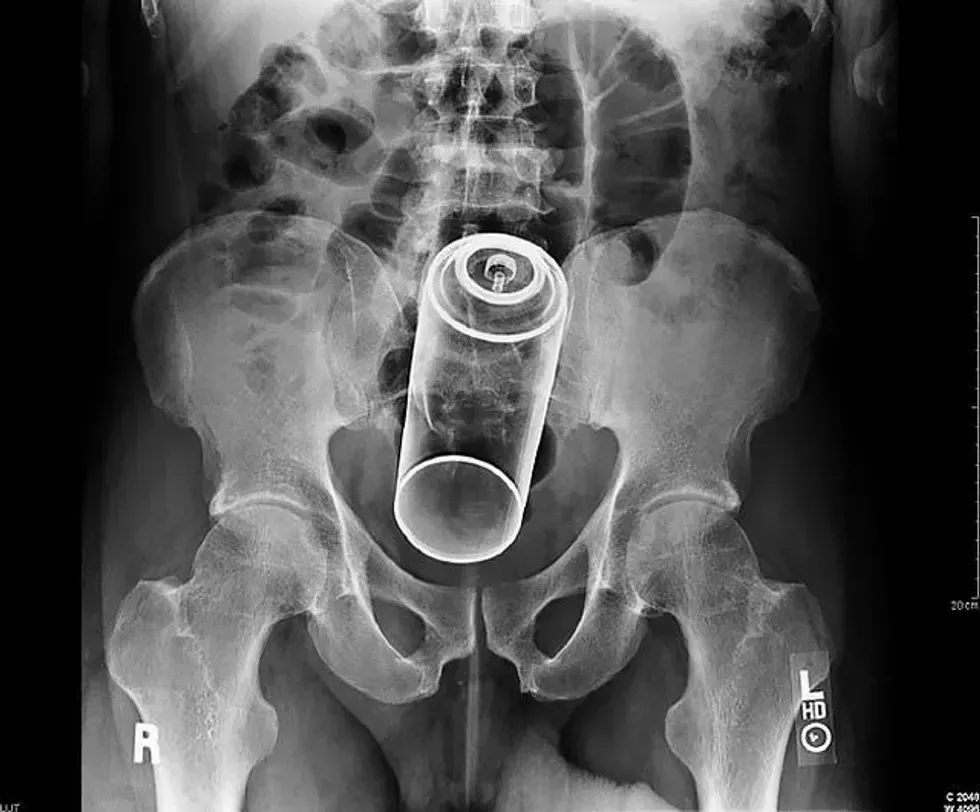

8. A flash light